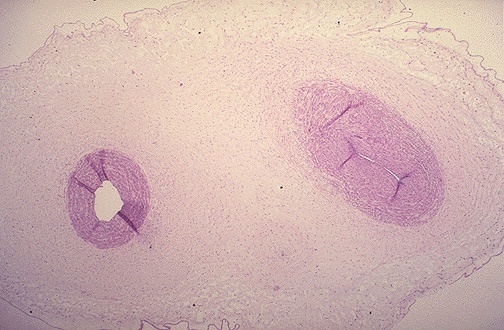

Image 5.4

The umbilical cord of the first twin is shown here. What do you notice?